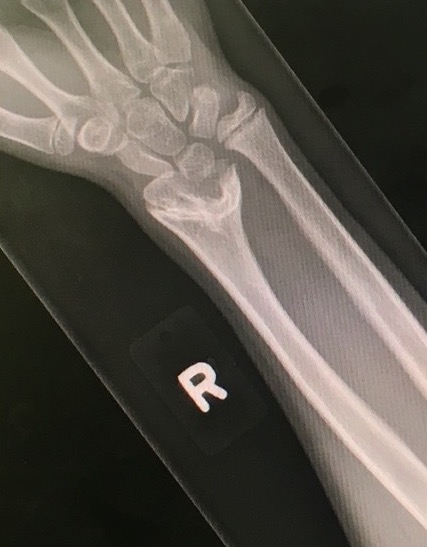

Xray